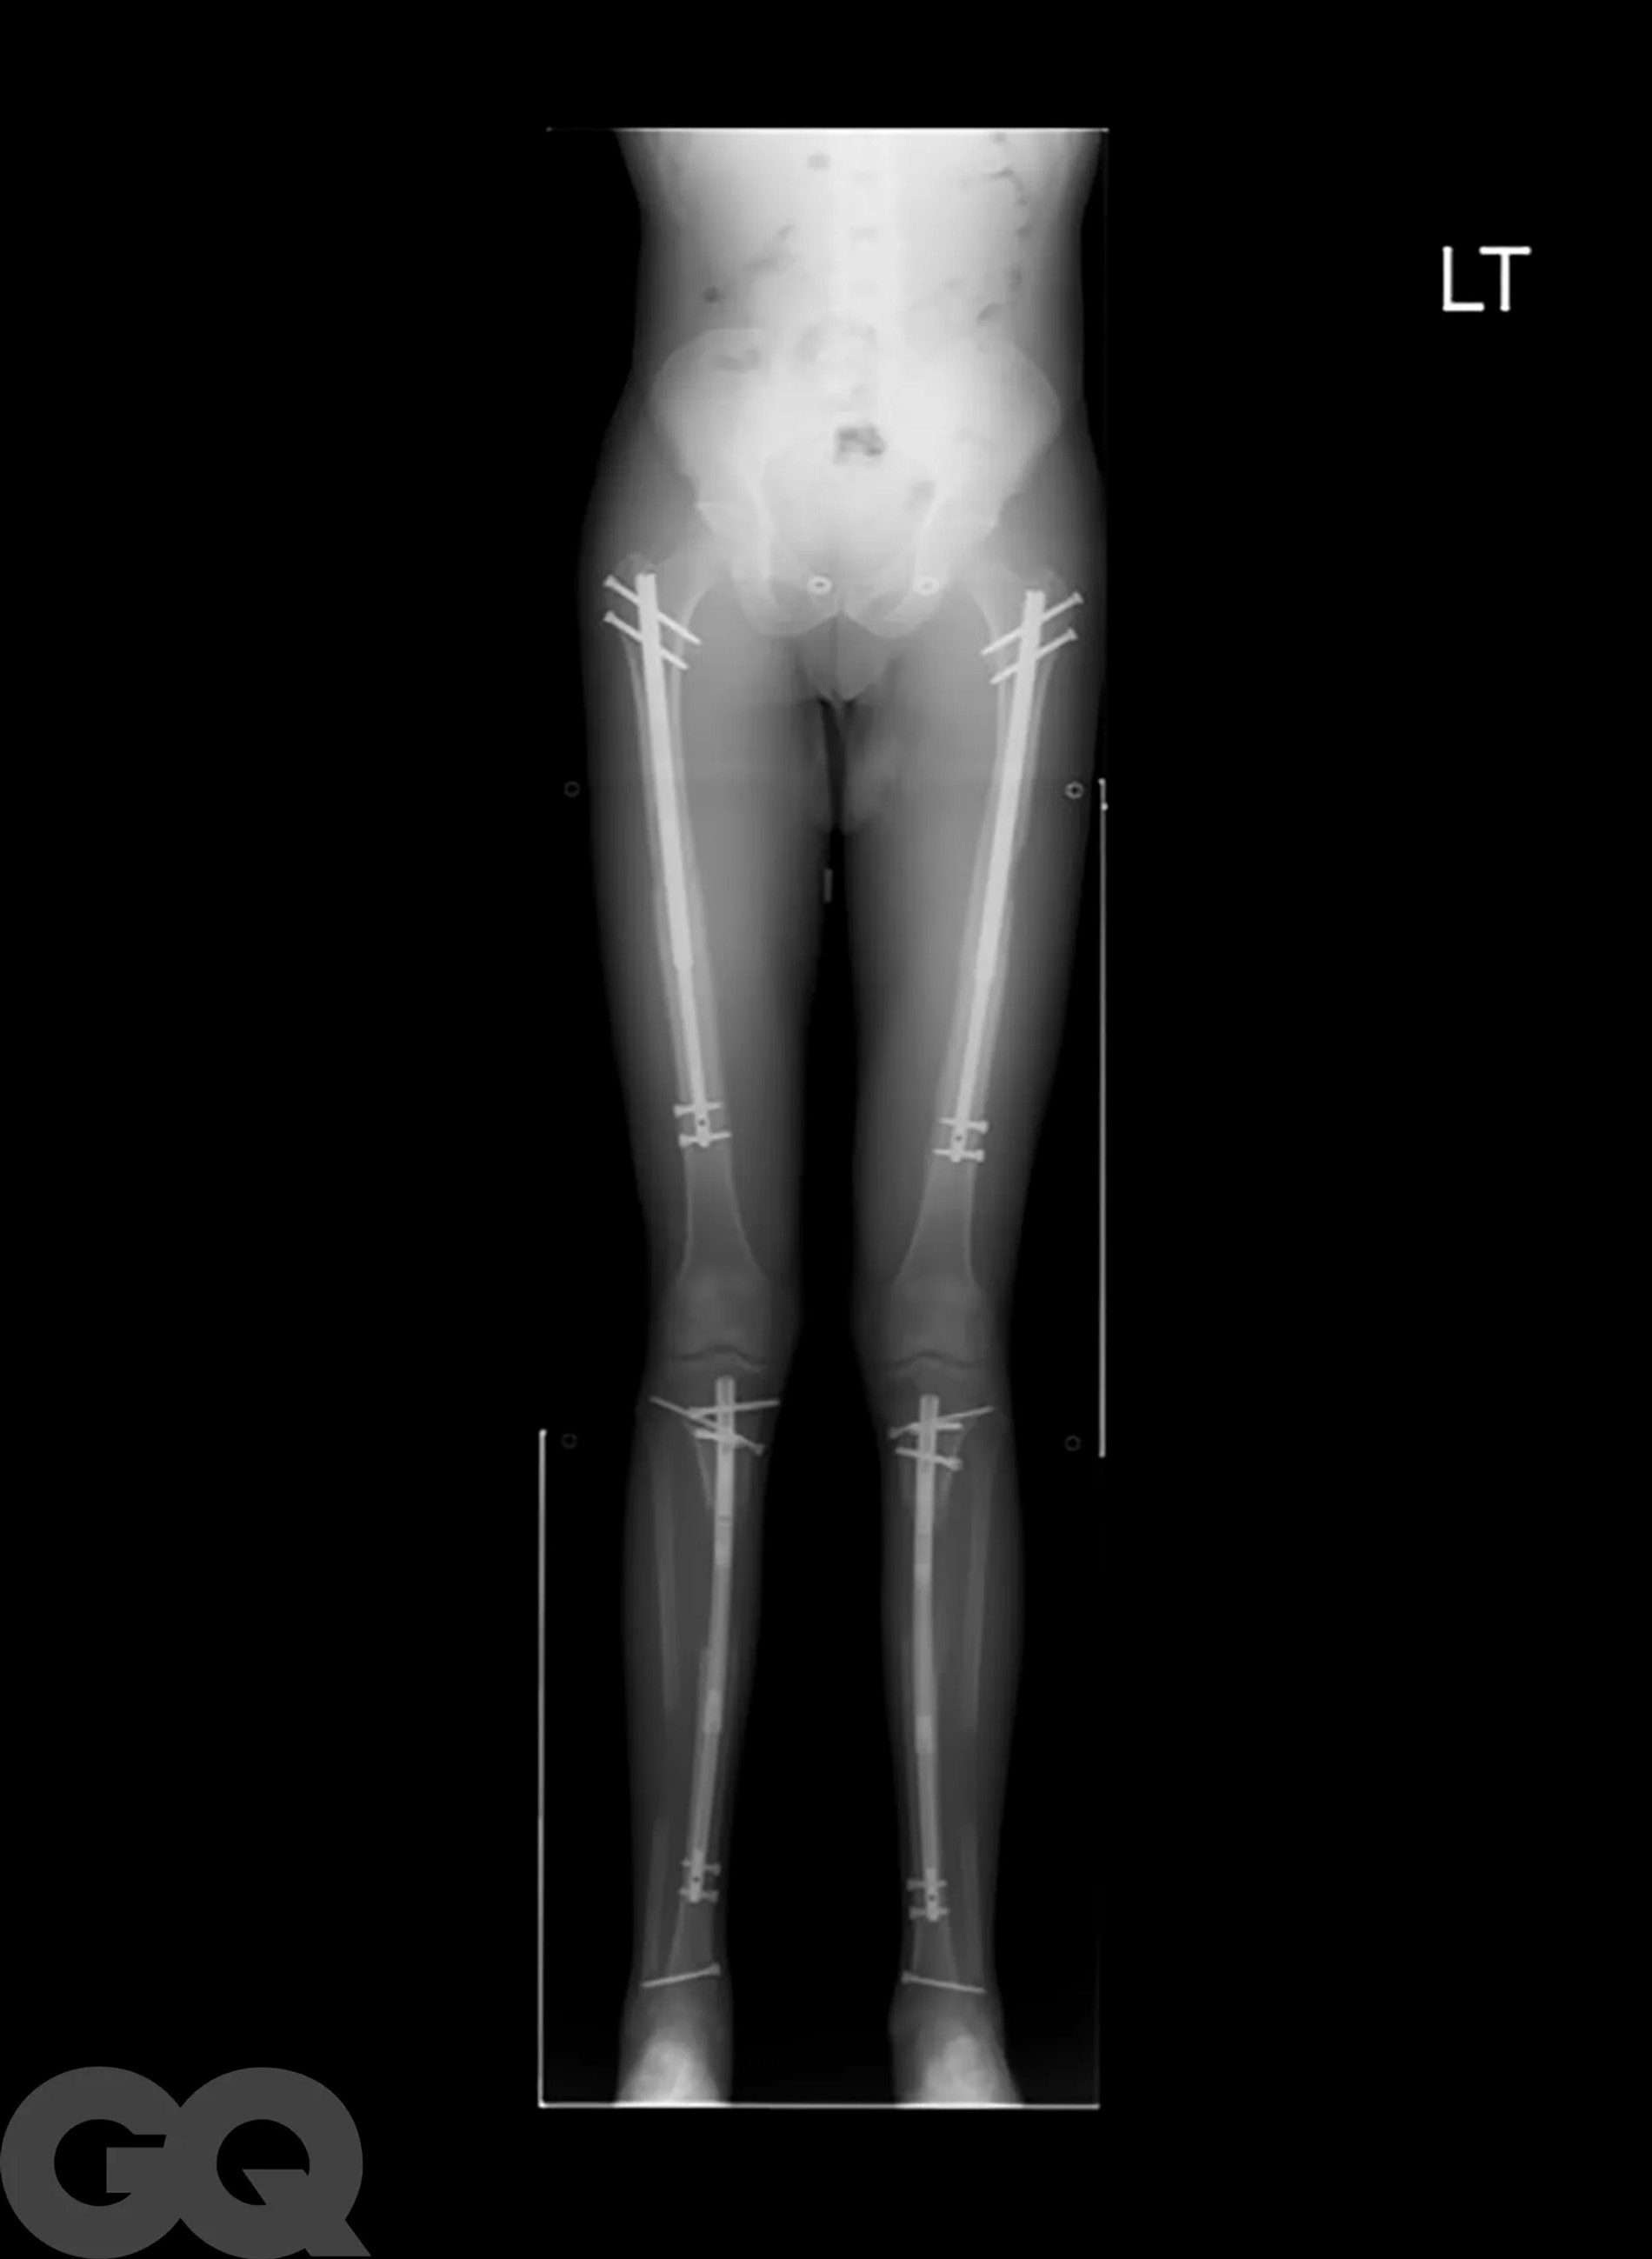

Надо сказать, что операция эта больше напоминает самую настоящую экзекуцию. Она основана на методике советского хирурга-ортопеда Гавриила Илизарова, которая изначально была разработана для пациентов со сложными переломами костей. Американские специалисты ее доработали и сделали более щадящей, но все же. В погоне за несколькими добавочными сантиметрами мужчины соглашаются на то, чтобы их собственные бедренные кости были сломаны. Да, без этого никак.

После перелома между костями вставляют регулируемые титановые стержни, которые наращивают на один миллиметр каждый день в течение примерно 90 суток с помощью магнитного пульта дистанционного управления. Как только сломанные кости срастутся, человек становится выше ростом и снова может ходить. Обычно весь процесс занимает 1 год, реабилитация сопровождается болью, что нисколько не смущает мужчин, решивших немного подрасти.

Не останавливает их и тот факт, что удовольствие это, прямо скажем, из дорогих: мужчины раскошеливаются на суммы от 70 до 150 тысяч долларов, в зависимости от того, сколько дюймов они хотят нарастить. И даже берут на подобные цели кредиты! Большинство выбирают стандартные три дюйма — это при условии, что экзекуции подвергнутся только бедра. Если и этого недостаточно и хочется еще немножко подрасти, спустя время врачи предлагают таким же образом переделать и голени.